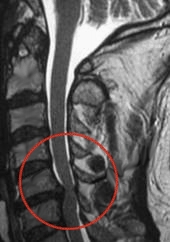

Bandscheibenvorfall der Halswirbelsäule |

Die Bandscheiben der Wirbelsäule befinden sich zwischen den Wirbelkörpern und funktionieren als bewegliche Stoßdämpfer bei allen Bewegungen des menschlichen Körpers. Sie bestehen aus einem elastischen inneren Gallertkern und dem äußeren Faserring. Im Bereich der Halswirbelsäule kommt es manchmal, mit zunehmendem Alter, durch Abnutzungserscheinungen, zu einer Schädigung des äußeren Faserringes und Teile der Bandscheibe treten in den Rückenmarkskanal vor - man spricht dann von einem Bandscheibenvorfall (Prolaps). Typisch dafür sind starke Nackenschmerzen ausstrahlend in den Arm, Taubheitsgefühle, bis hin zu zeitweise Lähmungserscheinungen im Arm oder in der Hand. Mittels CT oder MRT haben wir die Möglichkeit einen aufgetretenen Prolaps der Halswirbelsäule zu sichern um dann die Therapie der Wahl einzuleiten. Eine Besserung kann mit Physiotherapie, mittels Chirotherapie und der Gabe von Schmerzmittel erzielt werden, aber nicht selten ist eine operative Behandlung erforderlich in der die ausgetretenen Bandscheibenteile mittels minimal- invasiver neurochirurgische Engriffe, entfernt werden und dadurch eingeklemmte Nervenwurzeln entlastet werden. |